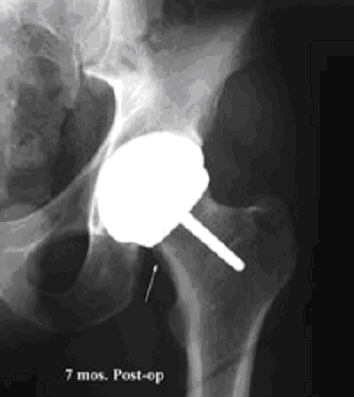

Hi-Tech Orthopedic Braces Result in a Better fit